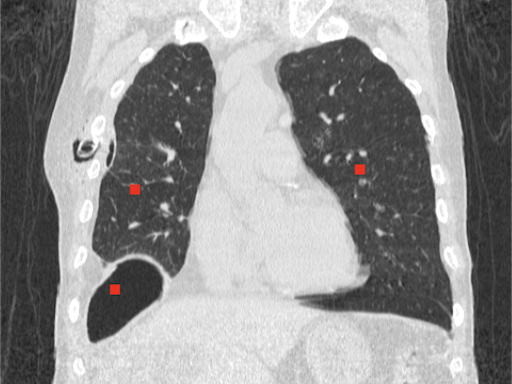

# Image source: Case courtesy of Tariq Walizai, Radiopaedia.org, rID: 184833

# https://radiopaedia.org/cases/184833?lang=us

image = Image.open("path-to-resources/chest-tube.jpg").convert("RGB")

seed_points = [[135,235],

[360,215],

[115,335]] # (X,Y) coordinates of points

color_values = [(255, 0, 0),

(0, 255, 0),

(0, 0, 255)] # (R, G, B)

tolerance = 2